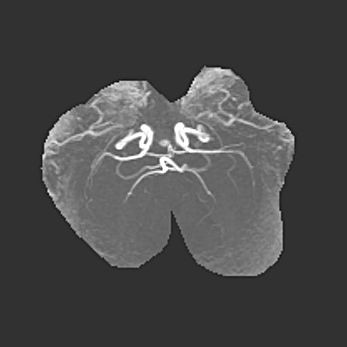

мрт снимки

Ниже представлена  галерея МРТ снимков, полученных с применением LMT неонатальных матричных РЧ катушек. Также каждая группа МРТ снимков сопровождается информацией о пациенте (диагноз, возраст, вес, пол, срок гестации) и краткой сопроводительной расшифровкой диагноза.

Церебральная ишемия II.

Возраст: 5 дней

Вес: 3400 г

Пол: женский

Окружность головы: 35 см

Срок гестации: 39 недель

Церебральная ишемия – это заболевание, характеризующееся недостаточностью (гипоксией) либо полным прекращением (аноксией) снабжения мозга кислородом по причине закупорки одного или нескольких сосудов. Это приводит к  что метаболическим расстройствам различной степени тяжести в тканях головного мозга, развитию коагуляционных некрозов и гибели нейронов.